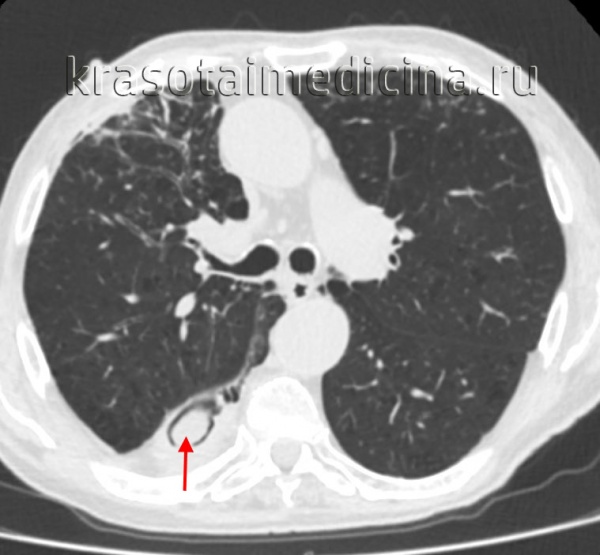

- Рентгендиагностика. При проведении бронхографии и компьютерной томографии выявляются проксимальные бронхоэктазы, «летучие» инфильтраты в легких.

- Лучевая диагностика.Рентгенологическая картина в легких отличается разнообразием. Определяются нестойкие эозинофильные инфильтраты, плотные округлые или шаровидные тени с полостями распада, расположенные преимущественно в верхних долях лёгких, мелкоочаговая диссеминация. Характерным признаком аспергилломы является наличие серповидного просветления в полости округлого или овального образования, которое смещается при изменении положения тела (симптом погремушки). При заполнении полости аспергилломы контрастом грибные массы всплывают (симптом поплавка).

КТ ОГК. Полостное объемное образование в нижней доле правого легкого, частично заполненное грибковыми массами.